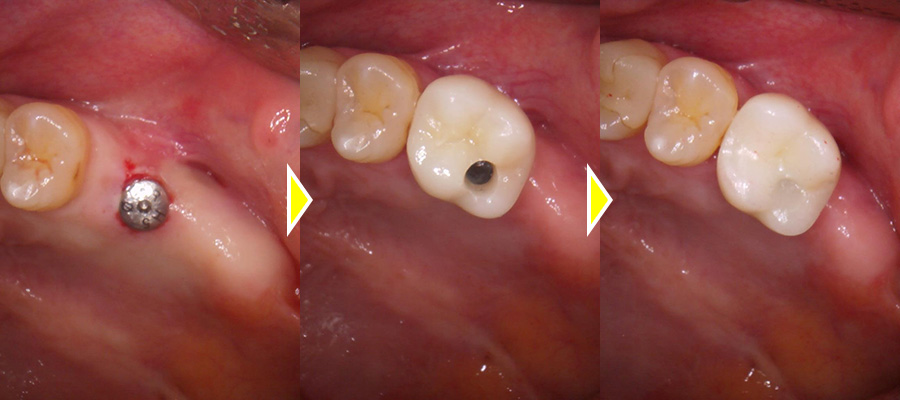

5ヶ月し、骨化を確認した後インプラントオペを行いました。

インプラント埋入後3週で抜糸を行い、3ヶ月おいてから二次オペを行いオステオインテグレーションを確認し、型取りを2度行い上部に歯をセットしました。

上部構造(人工歯)の装着・治療完了

本来大臼歯は2本ある為、この患者さまの場合2本インプラントを入れることが理想的だが、今回は金額をなるべく抑えたいとのことで、6番の歯のみインプラントを埋入し、短縮歯列にしています。

術後は奥歯で硬いものもしっかりと噛むことができるようになり、大変満足していただいています。